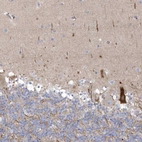

Immunohistochemical staining of human cerebellum shows strong cytoplasmic positivity in Purkinje cells.